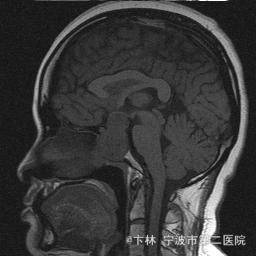

40岁女性,因“双眼视力下降三月余伴停经1个月余”入院。 患者三月前无明显诱因下出现双眼视力下降,视物模糊,尤以左眼为甚,只能近距离看到手动,无头痛、头晕,无恶心、呕吐,无视物旋转,无行走困难等不适,患者曾在某眼科医院就诊治疗,考虑为双眼视神经炎,予以营养,补液对症等治疗(具体不详),情况不见好转,近一月来患者月经停止,来我院神经外科门诊,予以查头颅CT,头颅MRI,提示“垂体大腺瘤”,为求进一步治疗收住入院

予以完善血,尿,粪常规检查,及凝血功能全套,输血功能全套及垂体功能全套,蝶鞍冠状CT等术前检查措施,行经蝶入路垂体瘤切除术。术后予以对症,补液,调节血电解质等治疗,患者视力明显改善,复查头颅MRI提示肿瘤基本全切,一周后患者出院。

此病人颅内垂体瘤体积较大,突破鞍隔压迫视交叉,故患者视力视野障碍为首发症状,该肿瘤主体有大部分向蝶窦腔生长,因此采用经蝶手术入路,肿瘤切除满意,术后患者视力视野恢复满意,。